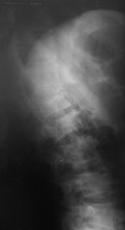

Рис. 12. КТ и рентгенограммы пациента А. 15 лет. Взрывной перелом Th9, Th12. Компрессионный перелом Th10.

А, Б – КТ до операции; В, Г – рентгенограмма после дорсальной непрямой репозиции, фиксации и заднего локального спондилодеза |